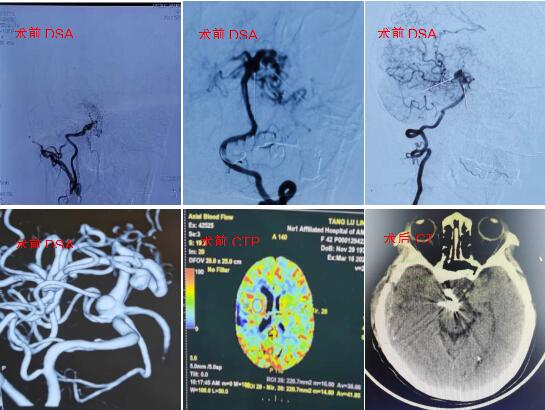

患者唐某,42岁,女性,来自合肥庐江县,系“头晕一月余”就诊于当地医院,CTA提示烟雾病合并基底动脉尖以及右侧大脑后动脉P2段动脉瘤,遂来我院进一步诊治。入院后行全脑血管造影检查,确诊烟雾病合并基底动脉尖以及右侧大脑后动脉P2段动脉瘤,同时CTP提示右侧脑灌注减低。经科室讨论后拟定治疗方案如下:1.先行血管搭桥治疗烟雾病,二期处理颅内动脉瘤;2.先行介入支架辅助栓塞治疗颅内动脉瘤,二期治疗烟雾病,但栓塞术后长期口服抗凝药影响后续治疗;3.同期行颅内后循环多发动脉瘤颅夹闭及右侧血管搭桥加颞肌贴敷。这样既可以解决颅内多发动脉瘤,又能通过搭桥提高右侧脑组织血流量,降低烟雾病导致梗塞风险。但是手术难度大,风险高。与家属充分沟通后,家属选择开颅动脉瘤夹闭+血管搭桥术。

该手术由胡阳春副主任医师主刀完成,王晓健副主任指导。手术选择从右侧颞下入路,首先暴露右侧大脑后动脉P2段动脉瘤,将动脉瘤瘤颈塑性夹闭后,继续探查基底动脉尖部,选择合适角度动脉瘤夹2枚塑形夹闭动脉瘤;再行脑血管搭桥+颞肌贴敷术术后患者一般情况良好,肢体活动正常。